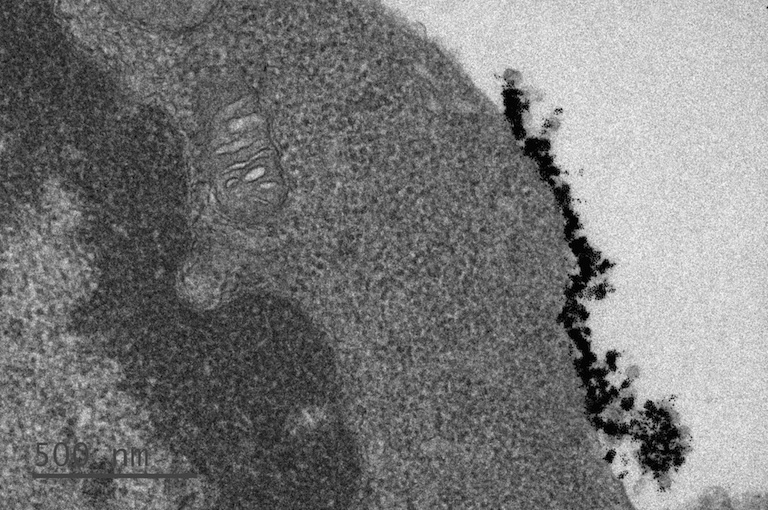

Cytosolic drug transportation is crucial for effective treatments. Two of the major challenges are for drugs to reach the target tissues and then on a subcellular level, to escape from endosomes and reach their targeted sites in the cytosol. We tackled this problem by using amphiphilic nanoparticles (amph-NPs) as cytosolic drug carriers. These particles embed and traverse lipid membranes reversibly without membrane disruption. Amph-NP can carry small molecule drugs effectively into numerous cell lines by embed in and traverse in between intracellular membranes. We aim to enhance immunomodulatory drug delivery of immune-compromised animal models via amph-NP drug transportation.